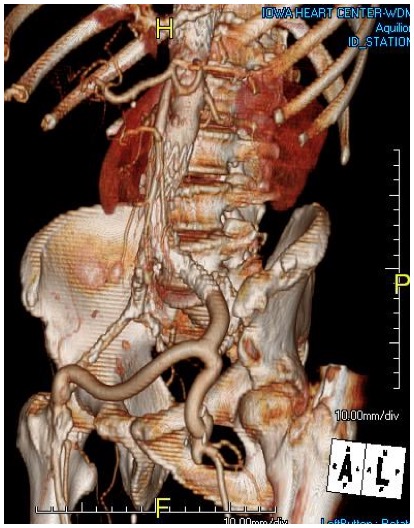

Looking back at his records, for three years he had multiple CT scans for abdominal pain showing the AAA and a well documented record of growth of about 2-3mm annually -the normal growth rate. He asked me to prognosticate and so I relayed that 4.7cm in 2017 with a 3mm growth rate, we would be operating in 2020. The anatomy was favorable with a long infrarenal neck and good iliac arteries for distal seal and access. He was quite anxious as whenever he had abdominal pain, his local doctors would discuss the AAA and its risks or order a CT. After a long discussion and considerable lobbying by the patient and family, I agreed to repair his 4.7cm AAA.

The EVAR was performed percutaneously. No endoleak was detected by completion arteriography (figure). He was soon discharged and was grateful. In followup, CT scan showed excellent coverage of the proximal and distal zones and absence of type III endoleaks. There was increased density to suggest a type II leak, but his inferior mesenteric artery was not the source of it. over a three year period, his aneurysm sac continued its 2-3mm of annual growth despite the presence of the the stent graft.